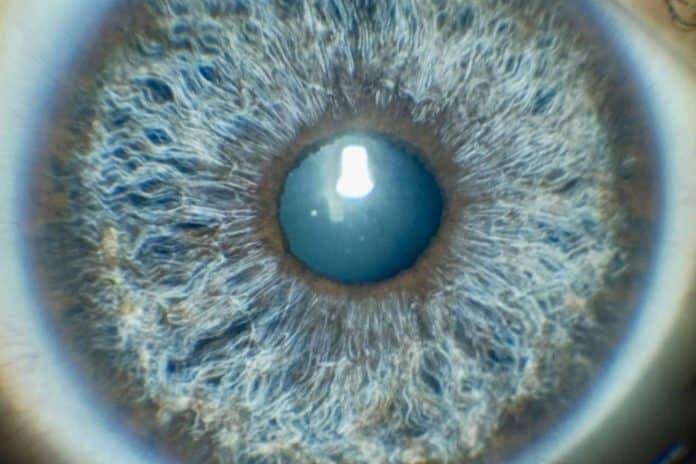

La innovadora aplicación Simulator 3D, desarrollada por Eyecos, tiene la capacidad de generar modelos tridimensionales de los ojos originales del paciente. Además de simular los resultados predichos por la aplicación Predictor, el Simulator 3D puede representar el efecto de la iluminación ambiental en la apariencia del color de ojos, en la dilatación de la pupila y en la variación de intensidad del color con precisión. Asimismo, la aplicación de Eyecos automatiza la generación de modelos de ojos tridimensionales, permitiendo al paciente comparar el efecto cosmético del láser antes y después del procedimiento.

Estas herramientas se pueden descargar fácilmente en dispositivos iOS y Android, para capturar imágenes de alta calidad de los ojos y obtener una simulación dinámica en 3D del cambio de color de ojos. Con estas aplicaciones, Eyecos respalda los resultados de sus tratamientos, con una previsualización accesible y realista de cómo sus pacientes se verían con un cambio de color de ojos.